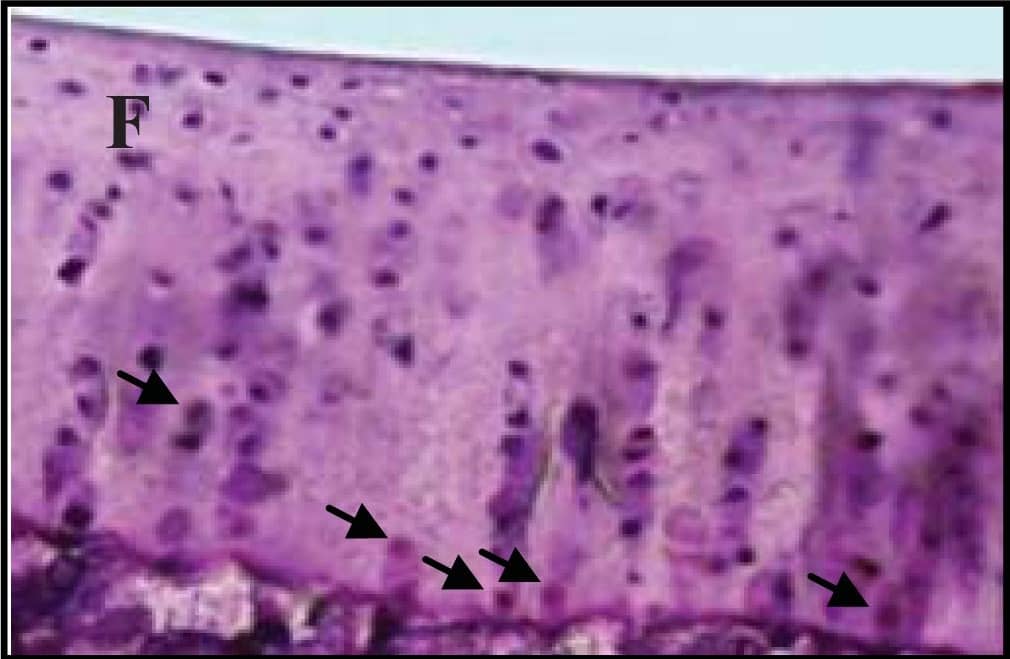

Detection of Mouse Caspase-3 by Immunocytochemistry/Immunofluorescence

Hepatocyte ARNT deletion alters fibrotic and apoptotic gene expression in the TAA model of fibrosis.Results for FC are shown in black columns and LARNT in white columns. Results are expressed relative to FC level. (A) Messenger RNA expression of ARNT and collagen isotypes. (B) Expression of genes regulating fibrosis in FC and LARNT mice. (C) F4/80 and inflammatory cytokine expression in FC and LARNT mice. (D) Apoptotic gene expression in FC and LARNT mice. (E) Representative histology of FC liver stained with anti-Caspase 3 at 100X magnification. (F) Representative histology of LARNT liver stained with anti-Caspase 3 at 100X magnification. (G) Average Caspase 3 positive cell counts per field of view at 100 X magnification. Mean±SEM, * = p<0.05 ** = p<0.01, *** = p<0.001. N = 5-6/group. Image collected and cropped by CiteAb from the following publication (https://dx.plos.org/10.1371/journal.pone.0121650), licensed under a CC-BY license. Not internally tested by R&D Systems.